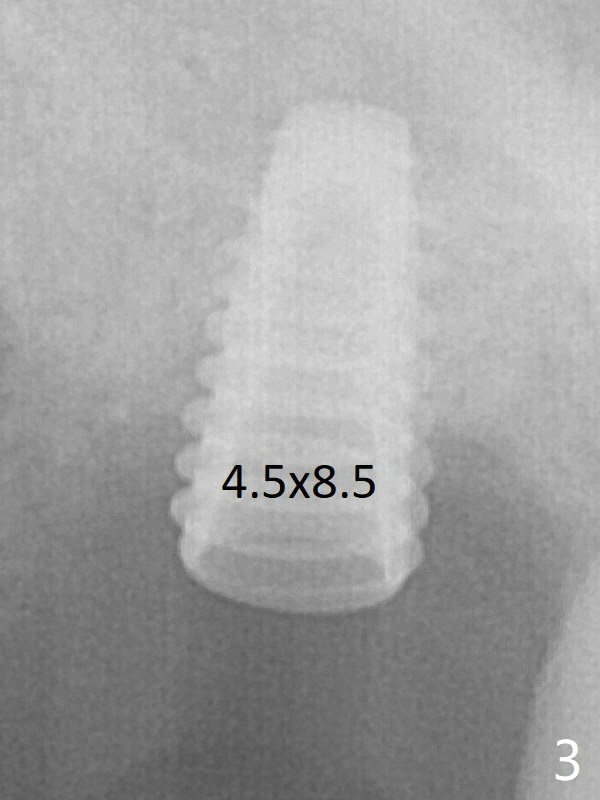

Sinus lift is accomplished with RT3 and autogenous bone prior to placement of a 4.5x8.5 mm implant (Fig.3). Because of flapless surgery and tight and long gingiva, bone graft around the coronal end of the implant is intentionally not placed. A 5.5x5(4) mm abutment is immediately placed for an immediate provisional. The provisional dislodges 3.5 months postop (Fig.4); impression is taken. The patient reports hot sensitivity and pain after meal at the implant site (Fig.5). After removal of the implant crown/abutment, she feels better.